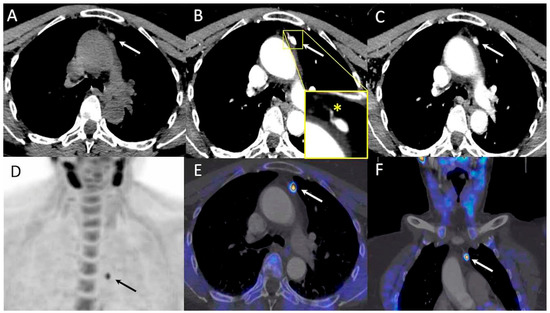

- Piccardo, A.; Trimboli, P.; Rutigliani, M.; Puntoni, M.; Foppiani, L.; Bacigalupo, L.; Crescenzi, A.; Bottoni, G.; Treglia, G.; Paparo, F.; et al. Additional value of integrated 18F-choline PET/4D contrast-enhanced CT in the localization of hyperfunctioning parathyroid glands and correlation with molecular profile. Eur. J. Nucl. Med. Mol. Imaging 2019, 46, 766–775. [Google Scholar] [CrossRef]

- D’Agostino, J.; Diana, M.; Vix, M.; Nicolau, S.; Soler, L.; Bourhala, K.; Hassler, S.; Wu, H.S.; Marescaux, J. Three-dimensional metabolic and radiologic gathered evaluation using VR-RENDER fusion: A novel tool to enhance accuracy in the localization of parathyroid adenomas. World J. Surg. 2013, 37, 1618–1625. [Google Scholar] [CrossRef] [PubMed]